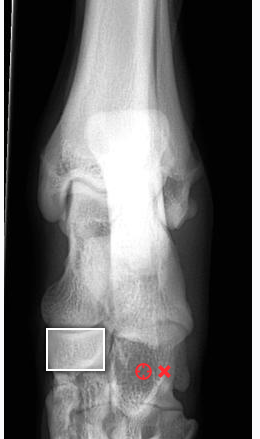

The most distal joint

Tarsometarsal joint

Box?

Red x?

Central tarsal bone

Red x- fourth tarsal bone